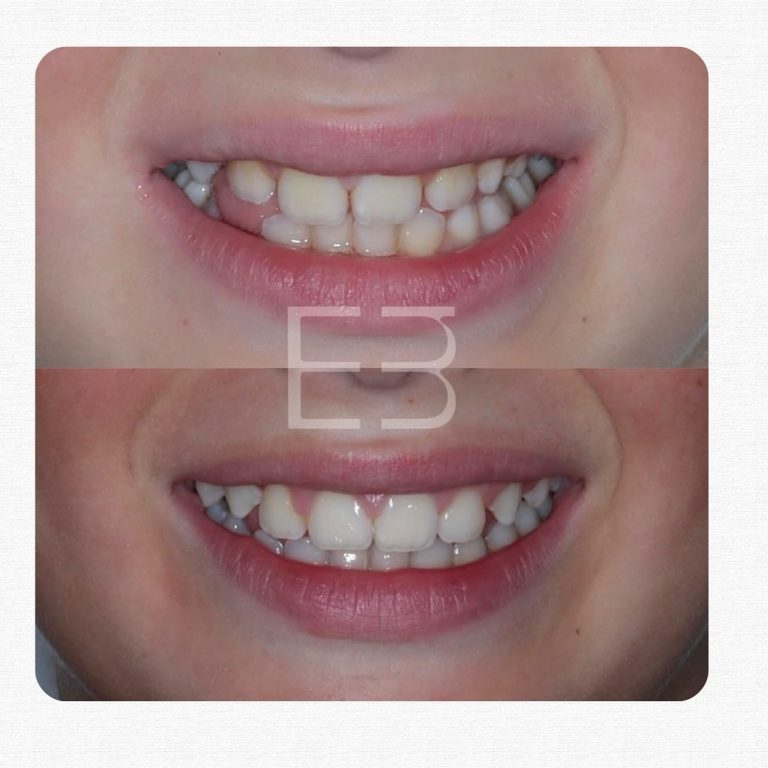

Casos reales de antes y después

Cada sonrisa tiene una historia. En Clínica Dental Blaumar te mostramos casos reales de pacientes que confiaron en nosotros para mejorar su salud y su estética dental. Antes y después, procesos y resultados explicados con claridad, para que veas cómo trabajamos: con planificación, precisión y un trato cercano de principio a fin.